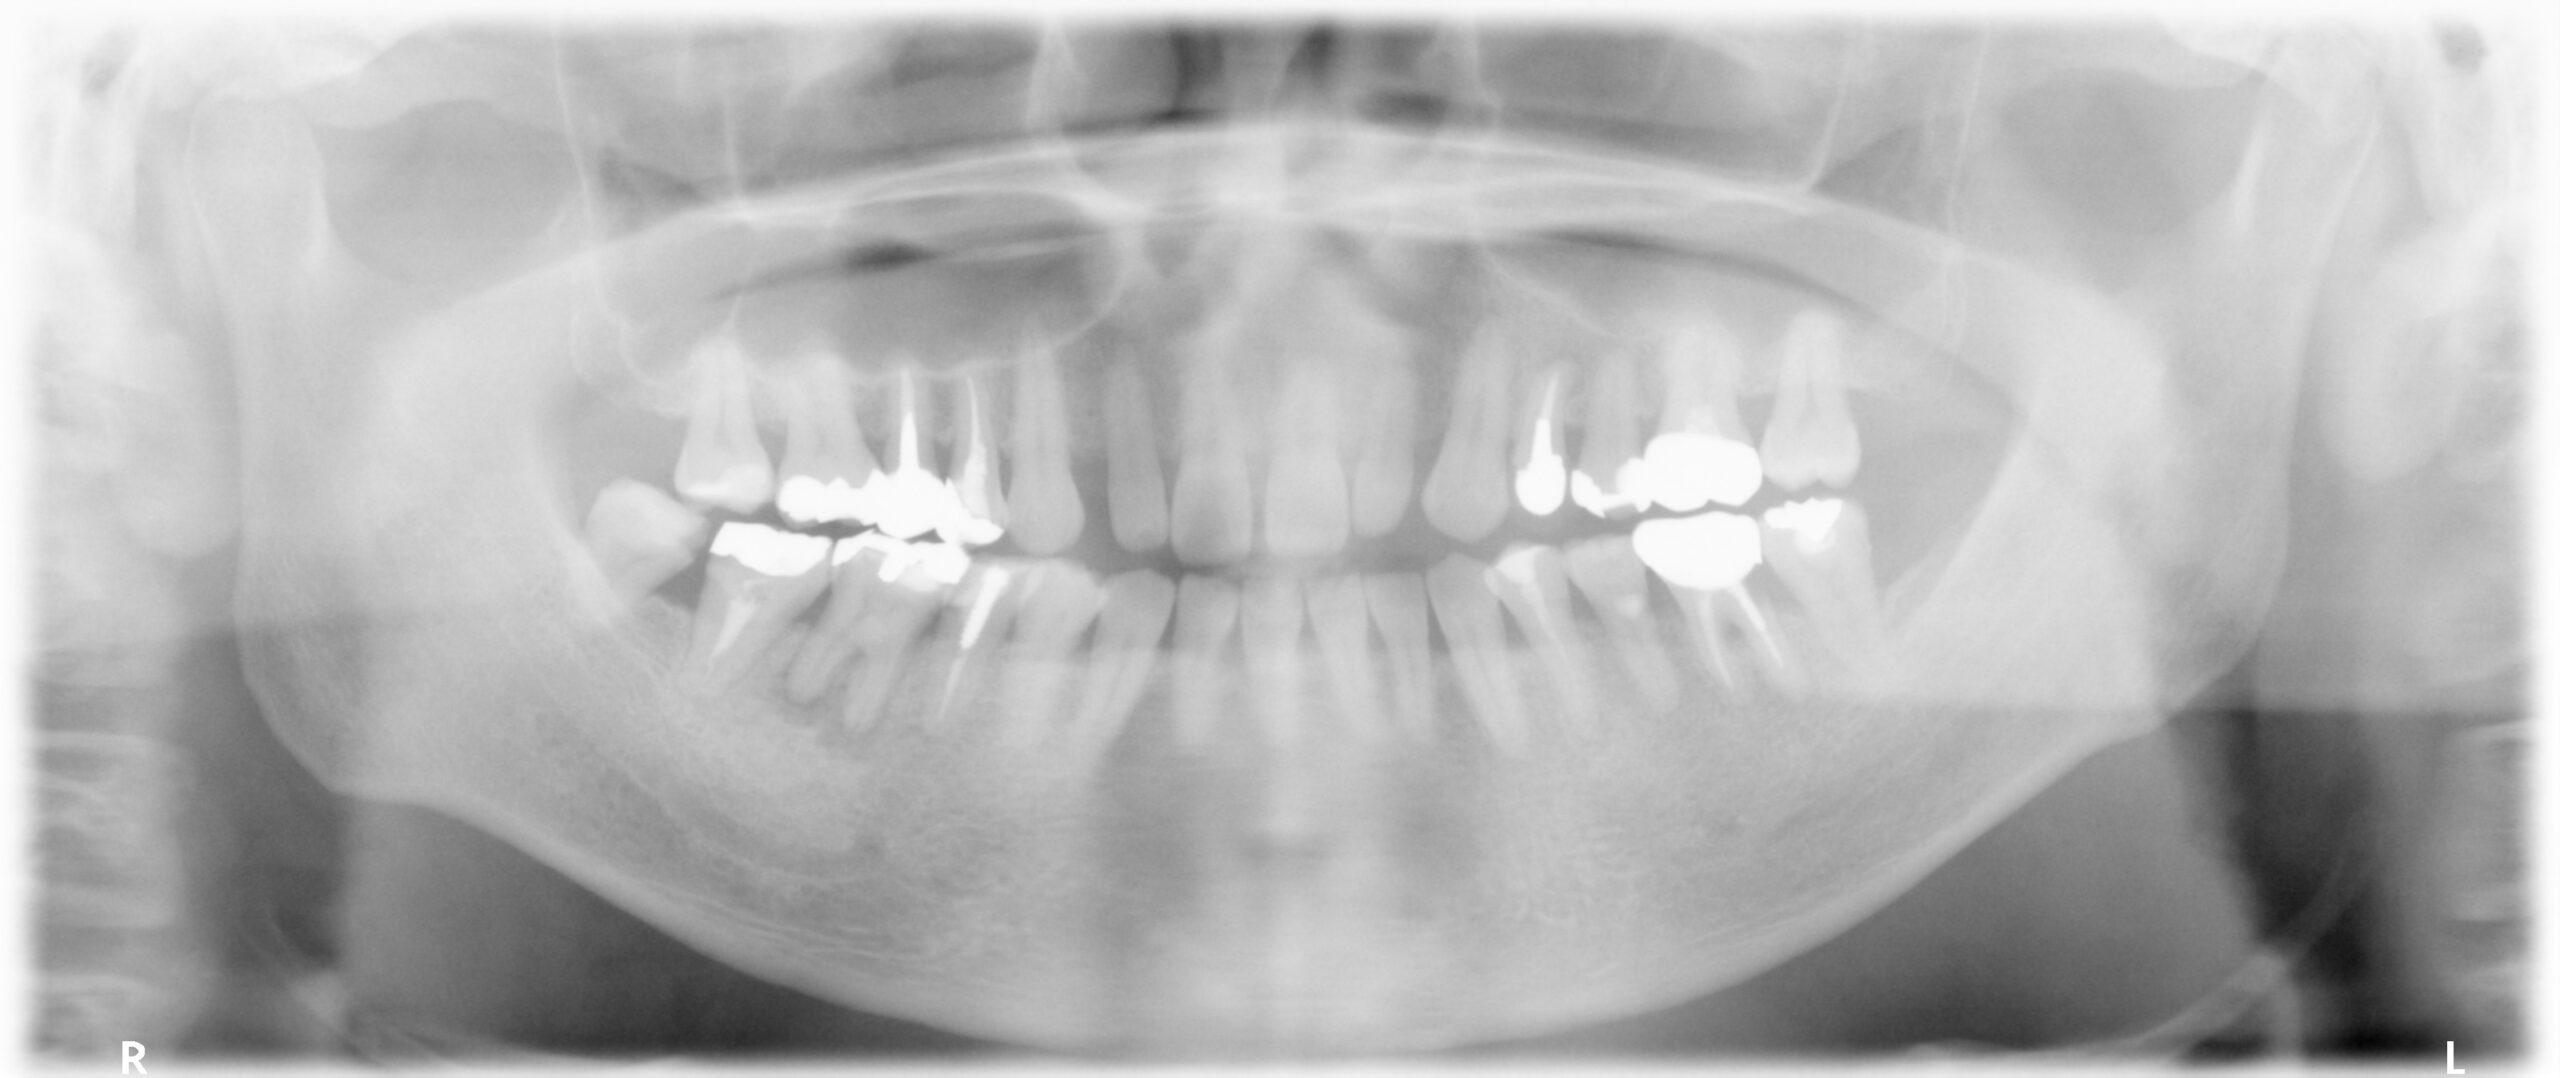

症例写真 レントゲン